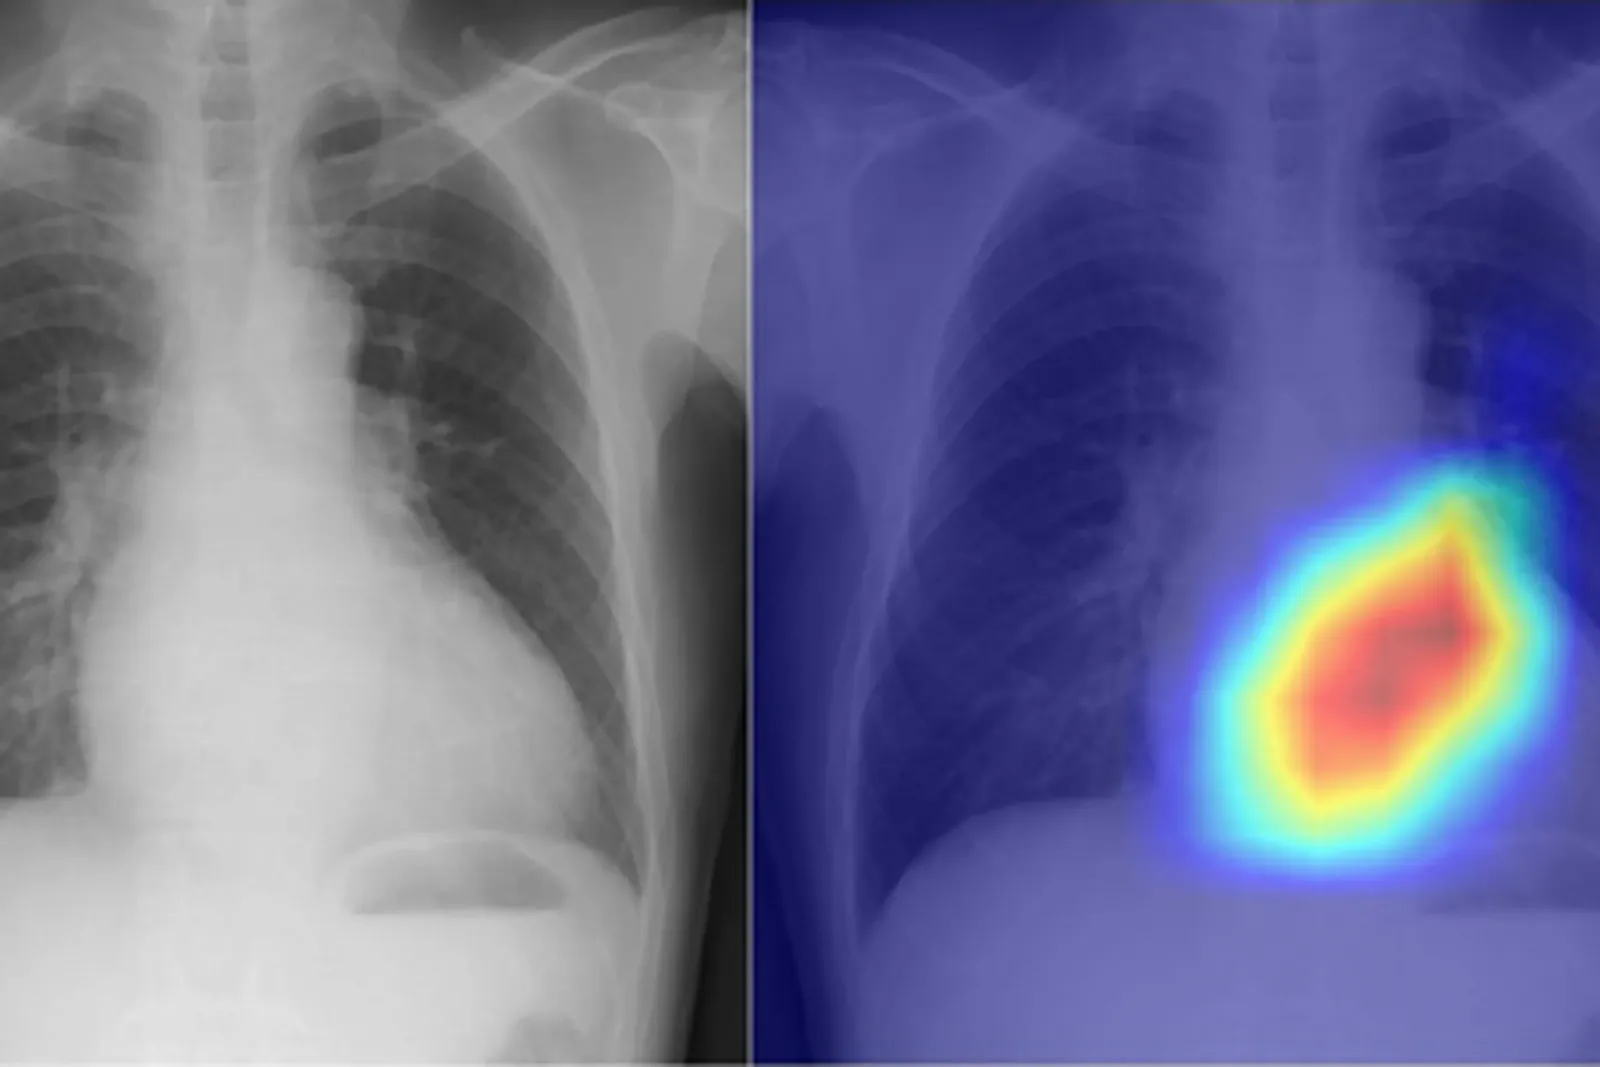

Рентген часто назначают самым разнообразным пациентам, однако он не даёт полной картины органов грудной клетки, поскольку представляет собой статичное изображение. Поэтому врачи вынуждены также назначать эхокардиограмму, которая позволяет оценить эффективность работы клапанов сердца. Тем не менее не все пациенты могут пройти это обследование, к тому же для него нужен специалист с особыми навыками.

Поэтому исследователи из Осакского университета (Япония) разработали особую модель искусственного интеллекта, использующую глубокое обучение, чтобы превратить рентген в более подробный диагностический инструмент. Глубокое обучение — это процесс, который позволяет компьютеру буквально имитировать человеческий мозг для обработки данных. Модель способна распознавать сложные закономерности в тексте, изображениях, звуках и прочем.

Японский ИИ был обучен при помощи 22 551 рентгеновского снимка и такого же количества эхокардиограмм, полученных от 16 946 пациентов в 2013–2021 годах. Рентгеновские снимки были заданы в качестве входных данных, а эхокардиограммы — в качестве выходных, при этом модель должна была связать оба набора данных.

В процессе тестирования исследователи обнаружили, что ИИ способен точно классифицировать шесть типов пороков сердца. Точность модели при этом составила около 90%, что является очень высоким уровнем для такого типа программ. Команда надеется, что этот новый подход поможет врачам дополнить данные, полученные благодаря разным обследованиям, особенно когда требуется быстрая диагностика.